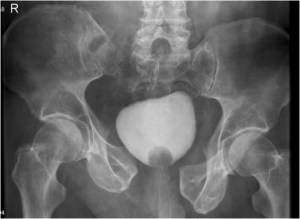

Acute Management of Pelvic Ring Injuries

Pelvic fractures

Femoral neck fractures |